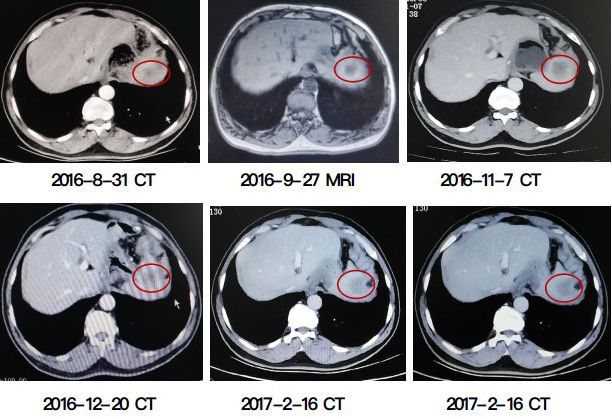

病情评估:患者为胃窦部中分化腺癌,术中探查无腹水,盆腔远处无转移结节,肝脏、胰腺、脾脏、膀胱、直肠、结肠、小肠及系膜未触及转移结节,胃窦近小弯侧触及肿瘤(4×3cm),质硬,侵及浆膜层,与周围脏器界限清楚。术后病理分期为IIIB期。免疫组化:Her-2(3 ),c-met(弱 ),Ki-67( ,60%),S-100染色提示神经侵犯,D2-40、CD34染色未提示脉管侵犯。 治疗方案:术后辅助化疗(SOX方案×5周期→S-1×3周期) 治疗经过:2015-7-18至2015-11-5给予SOX方案(奥沙利铂220mgd1 替吉奥40mg早饭后半小时,60mg晚饭后半小时d1-14),2015-11-29至2016-1-27因血小板低给予替吉奥40mg早饭后半小时,60mg晚饭后半小时d1-14单药化疗3周期。 客观疗效:治疗期间复查肿瘤标志物及影像学均未提示局部复发及远处转移。 不良反应:2度(化疗期间血常规:血小板79×109,对症支持治疗后好转)。 疗效总结:患者病情平稳,未见复发及转移征象。 病情评估:肿瘤标志物(CA199)2016-6-27 48.02逐渐升高至2016-11-7 323.2U/ml。影像学CT(2016-8-31)肝左叶脾上缘处见1.8×1.5cm结节,边界模糊。MRI(2016-9-27)肝左叶外侧段见2.3×2.3×1.9cm信号欠均匀影。CT(2016-11-7)肝左叶脾上缘处见3.7×2.6cm结节,边界模糊。活检病理(2016-10-26):(肝脏肿瘤)腺癌,免疫组化CDX-2( ),Ki-67(60%) Her-2(2 ),Fish结果为基因扩增。 治疗方案:晚期一线治疗(HPF方案×6周期)。 治疗经过:2016-11-8至2017-2-16行曲妥珠单抗440mg静滴 顺铂110mg静滴 卡培他滨1500mg2次/日口服 d1-14。 客观疗效:肿瘤标志物(CA199)2017-2-3降至58.23U/ml。影像学CT(2017-2-16)肝左外叶转移瘤(2.3×2.3cm),缩小37%,达PR。见下图。 病情评估:2017-2-23行全麻下“肝转移癌切除术”,术中肝左外叶内可扪及包块,质硬,表面不平整,大小2.3×3cm,术后病理:查见腺癌,结合形态及病史考虑胃癌转移,肝切缘未查见癌组织。 治疗方案:术后辅助治疗(HPF方案×2周期→HF×2周期)。 治疗经过:2017-3-17至2017-4-16曲妥珠单抗440mg静滴 顺铂110mg静滴 卡培他滨1500mg 2次/日 口服d1-14治疗2周期;2017-5-13至2017-6-10曲妥珠单抗440mg静滴 卡培他滨1500mg 2次/日 口服d1-14治疗2周期。 客观疗效:肿瘤标志物(CA199)术后第2个周期降至正常,术后第4周期升至57.82U/ml。 影像学 CT(2017-4-8)肝左叶局部术后缺如。CT(2017-6-30)肝左叶局部术后缺如,新发低密度灶(1.2cm)。见下图。 病情评估:2017-6-30CT评估病情进展,肝左叶新发转移灶(1.2cm)。 治疗方案:晚期二线治疗(HD方案×2周期)。 治疗经过:2017-7-8至2017-8-2行曲妥珠单抗440mg静滴 多西他赛120mg静滴治疗2周期。 客观疗效:肿瘤标志物(CA199)2017-8-17升至301.8U/ml。影像学MRI(2017-8-7):胃癌术后改变,肝左叶局部术后缺如,肝左叶内侧段异常强化影(1.6cm),考虑转移,疗效评估为PD(33%)。见下图。 病情评估:2017-8-7影像学评估:肝左叶新发转移灶化疗后增大(PD),于2017-8-24行“全麻下肝转移癌微波消融术”。术中超声造影提示:肝左内叶病灶(2.2×2.8cm)呈“快进快出”模式,考虑为转移灶。 治疗方案:术后辅助治疗(HD方案×2周期→HDS方案×6周期)。 治疗经过:2017-9-7至2017-9-27行曲妥珠单抗440mg静滴 多西他赛120mg静滴治疗2周期。2017-10-17至2018-3-4行曲妥珠单抗440mg静滴 多西他赛120mg静滴 替吉奥40mg2次/日口服 d1-14治疗6周期。 客观疗效:肿瘤标志物(CA199)2017-10-17降至213.4U/ml后2017-10-18再升至262.1U/ml,2018-3-21升至582.7U/ml。腹部B超(2018-1-18):腹主动脉旁肿大淋巴结(2.2×1.9cm)。腹部MRI(2018-3-6):肝门区、左叶内侧段多发转移瘤(2.1×1.4cm)。见下图。 病情评估: 2018-3-6影像学评估病情进展,肝门区、左叶内侧段多发转移瘤较前增多、增大,于2018-3-26行“全麻下肝占位射频消融术”。术后行腹主动脉旁淋巴结放DT:54Gy/18F,肝转移灶放疗DT:61.2Gy/18F。2018-7-16CT:双肺散在多发结节增大、增多。 治疗方案:晚期三线治疗(H XELOX方案×2周期)。 治疗经过:2018-6-11至2018-7-20 曲妥珠单抗440mg 奥沙利铂200mg 卡培他滨1500mg2次/日 口服 d1-14治疗2周期。 客观疗效:肿瘤标志物(CA199)2018-7-16降至239.0U/ml。影像学未复查。见下图。 2.由于是单个肝脏病灶转移,因此在经过赫赛汀联合化疗达到PR的最佳疗效时,接受了手术治疗,但术后的DFS仅4个月,肝转移灶手术前后同时接受赫赛汀联合化疗。目前胃癌肝转移的手术指征也是针对寡转移灶的患者,虽然术后很快复发,但是并不能就此否定肝转移灶手术的价值。 3.该患者幸运的是转移病灶一直很局限,因此在系统性治疗的同时接受各种局部治疗,包括手术,射波消融和放疗,这个也是体现了综合治疗在晚期肿瘤中的治疗理念。 4.该患者的系统治疗中赫赛汀是跨线使用的。对于赫赛汀的跨线使用是否有获益,目前还没有成定论。主要是患者的个体化程度都很高,如果我们通过多次活检,或者液态活检能够有效地监测Her2 状态,是有利于我们决策在疾病进展后是否选用赫赛汀的。但目前的临床实践确实很难判断患者是否对赫赛汀真正耐药的。 5.像这样的患者,赫赛汀能否提前到术后辅助治疗阶段,是个很有意思的问题,但是目前缺乏强有力的证据。因此从治疗规范上来说,我们并不推荐赫赛汀用于Her2扩增的胃癌根治术后的患者接受辅助治疗。 (来源:《肿瘤瞭望》编辑部)